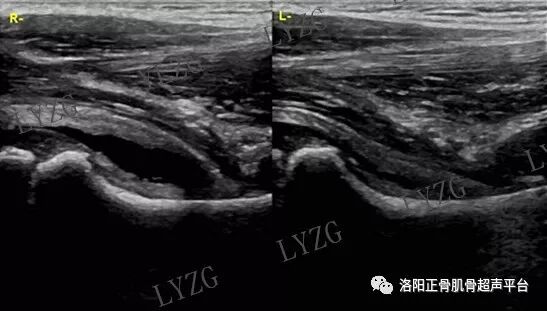

小儿正常髋关节超声表现

双侧髋关节前隐窝内均可见小于2mm的滑液

双侧髋关节前隐窝内均可见细带状滑液